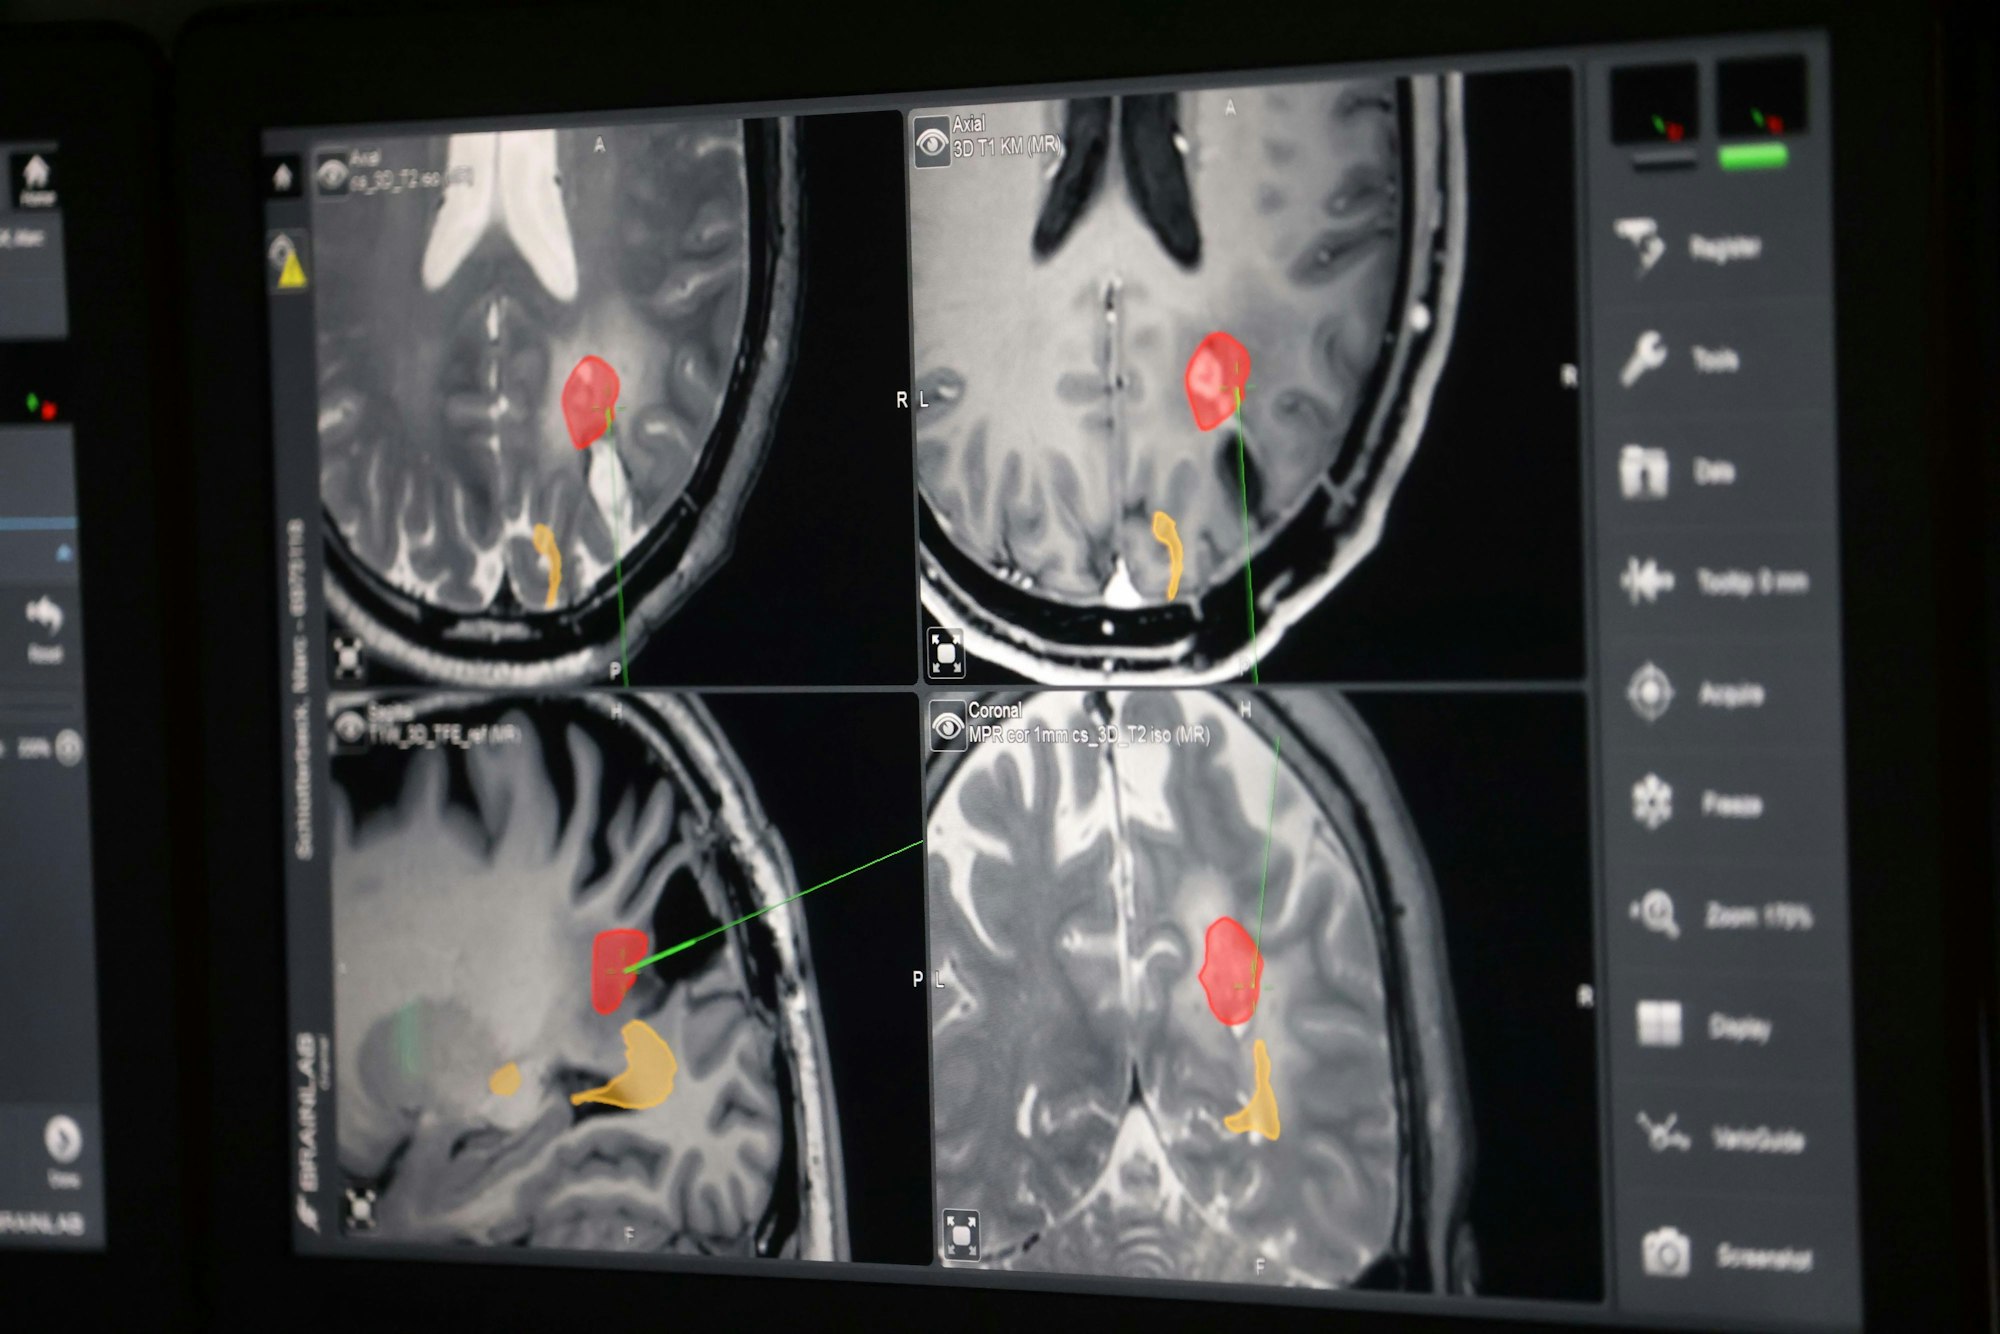

Im Schwarzlicht werden die Schnitte gesetzt, der Bildschirm zeigt die betroffenen Areale auf.

Der Tumor ist rot eingezeichnet, die Sehbahn gelb. Schwarz ist die Stelle der ersten Tumor-Entfernung.

Bei der zweiten OP weiß der Kölner, was auf ihn zukommt. Denn um möglichst viel vom Glioblastom zu entfernen, sind etliche Voruntersuchungen nötig. Mit der funktionellen Magnetresonanztomographie (fMRT) können aktivierte Hirnareale und Faserbahnen dargestellt werden. Bei Schlotterbeck sitzt der Tumor in der Nähe der Sehbahn. Im MRT muss er einfache Abbildungen erkennen und benennen: eine Blume, einen Löffel. Dabei wird die Aktivität der neuronalen Nervenbahn gemessen. In einem zweiten Verfahren wird ihm ein radioaktiver Stoff gespritzt, ein sogenannter Tracer. Das FET-PET ist ein Diagnoseverfahren der Nuklearmedizin. Mit einer Gamma-Kamera kann der Tumor genauer dargestellt werden. Die Uniklinik Köln ist eine von drei Kliniken in Deutschland, die alle Verfahren zusammenbringt. „Eigentlich müssen es alle so machen, aber es ist aufwändig und teuer“, sagt Goldbrunner.

Das eingeschaltete Schwarzlicht macht das Glioblastom sichtbar. Zusammen mit den MRT- und PET-Bildern, Ultraschall und der 5ALA-Methode ergibt sich ein genaueres Bild. Ein Bildschirm zeigt eine Art Landkarte des Gehirns – der Tumor ist rot eingefärbt, die Sehbahn gelb. Die Entfernung des Tumors beginnt: Eine Pinzette mit Strom schmilzt das mit Krebs befallene Gewebe weg. „Wir sind jetzt an der Sehbahn“, sagt Goldbrunner. Vorsicht ist geboten. Nach der OP wird Marc Schlotterbeck sagen, dass er dieses Mal keine Irritationen beim Sehen hatte. Nach der ersten Operation sah er einige Zeit bunte Ornamente an der weißen Krankenhauswand – eine Folge des Eingriffs so nah an der Sehbahn.